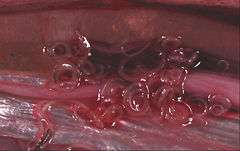

Diagnosis can be made by gastroscopic examination, during which the 2-cm larvae are visually observed and removed, or by histopathologic examination of tissue removed at biopsy or during surgery.